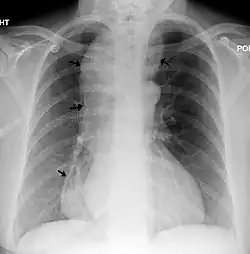

| A chest X-ray showing achalasia (arrows point to the outline of the massively dilated esophagus) | |

End-stage achalasia, typified by a massively dilated and tortuous oesophagus, may occur in patients previously treated but where further dilatation or myotomy fails to relieve dysphagia or prevent nutritional deterioration, and esophagectomy may be the only option.[16]